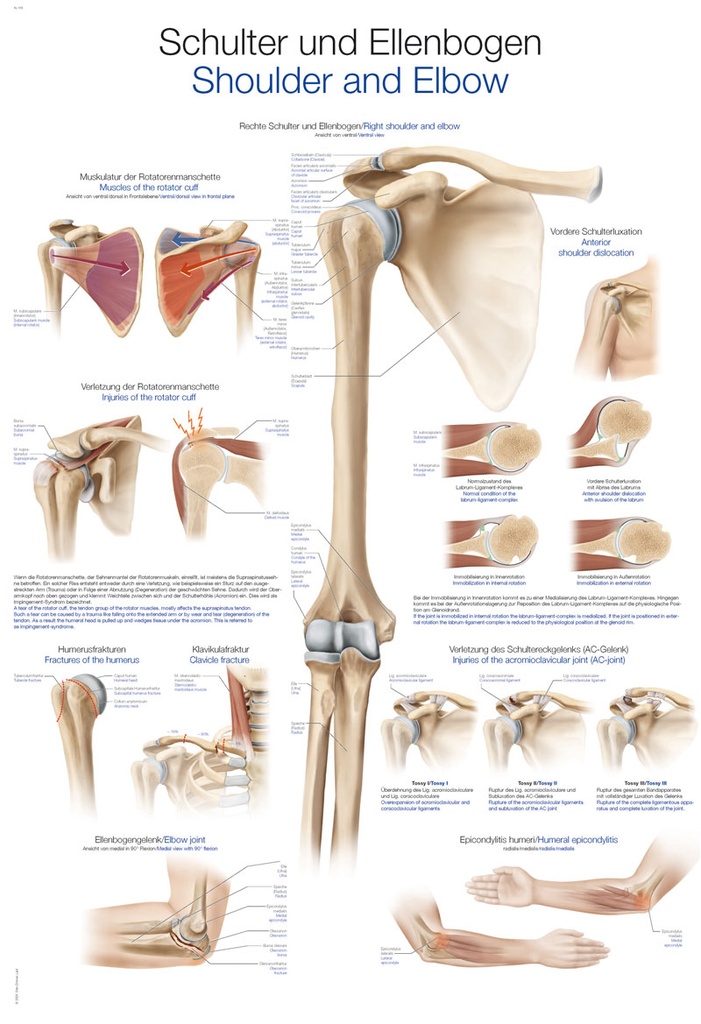

Beschreibungen in Englisch und Deutsch